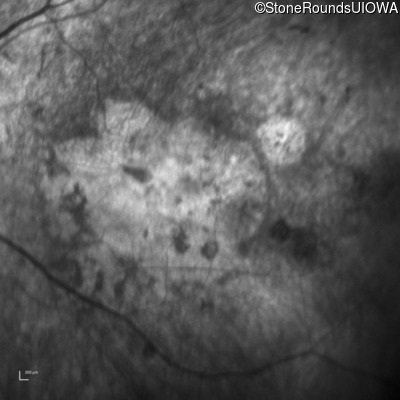

Infrared Fundus Photograph - Left - 10/300

Exemplar